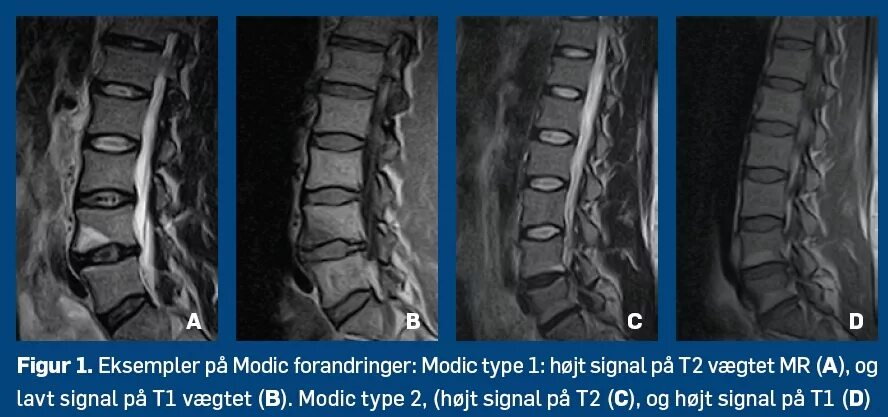

Изменение по типу modic 1